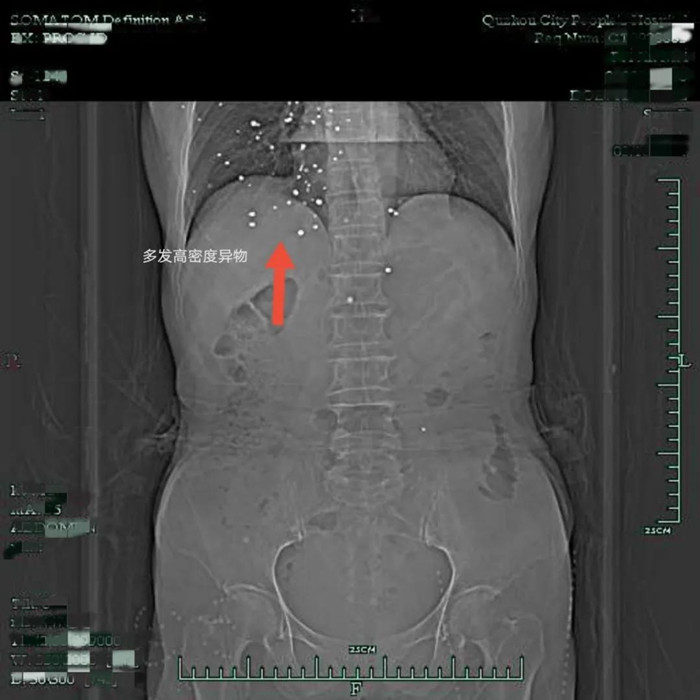

原以為這是一次普通的胃癌手術,沒想到裴阿姨入院后的胸部CT檢查結果,讓人大吃一驚——在裴阿姨右側胸廓皮下軟組織內、右肺、右側心包膜下、兩側心膈角區(qū)有散在結節(jié)狀致密影。

片子上這一顆顆密密麻麻的小白點是什么?

影像學上,這種密度高度懷疑是金屬滯留,為什么在裴阿姨的體內有多發(fā)金屬?

原來,裴阿姨曾在多年前遭遇過一次意外,導致散彈傷,而這次意外則給她后續(xù)的治療帶來了不小的難度。